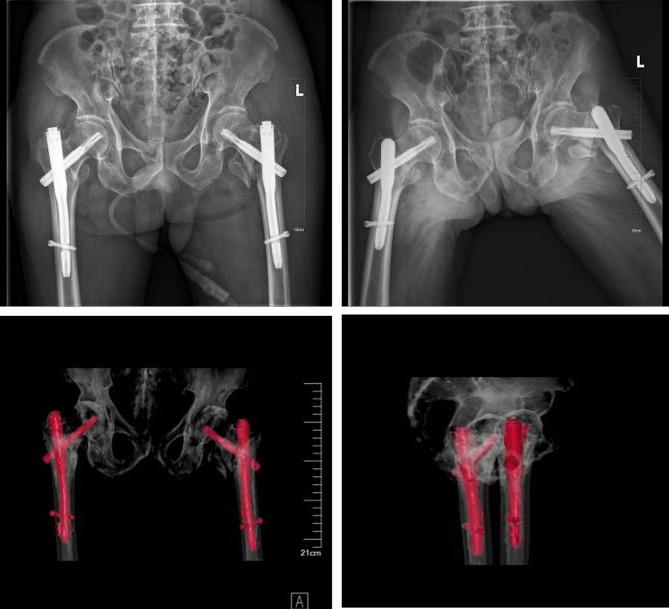

We report on an 84-year-old male who suffered severe trauma from a car accident, resulting in multiple injuries and shock state, with pain and limited mobility in both hip joints. After examination and imaging studies, the patient was diagnosed with multiple injuries and bilateral intertrochanteric fractures. Following emergency resuscitation, he was admitted to the orthopedic ward. A pre-surgical multidisciplinary team (MDT) consultation was convened to optimize surgical conditions. The patient underwent successful one-stage bilateral intramedullary nailing. The patient was assisted to stand with a walker on the third day after surgery. Six months post-surgery, the patient resumed outdoor activities.

Managing bilateral intertrochanteric fractures, particularly in the elderly with severe trauma, is notably challenging due to their rarity. However, a coordinated multidisciplinary approach and one-stage bilateral internal fixation can lead to effective treatment outcomes and favorable prognoses.

我们报告了一例 84 岁男性患者,因车祸遭受严重创伤,导致多发伤和休克状态,双侧髋关节疼痛且活动受限。经检查和影像学研究,患者被诊断为多发伤和双侧转子间骨折。在紧急复苏后,他被收入骨科病房。为了优化手术条件,进行了术前多学科团队(MDT)会诊。患者成功接受了一期双侧髓内钉固定术。术后第 3 天,患者在助行器的辅助下站立。术后 6 个月,患者恢复户外活动。

管理双侧转子间骨折,特别是对于严重创伤的老年患者,具有挑战性,因为其罕见。然而,协调的多学科方法和一期双侧内固定可以带来有效的治疗结果和良好的预后。